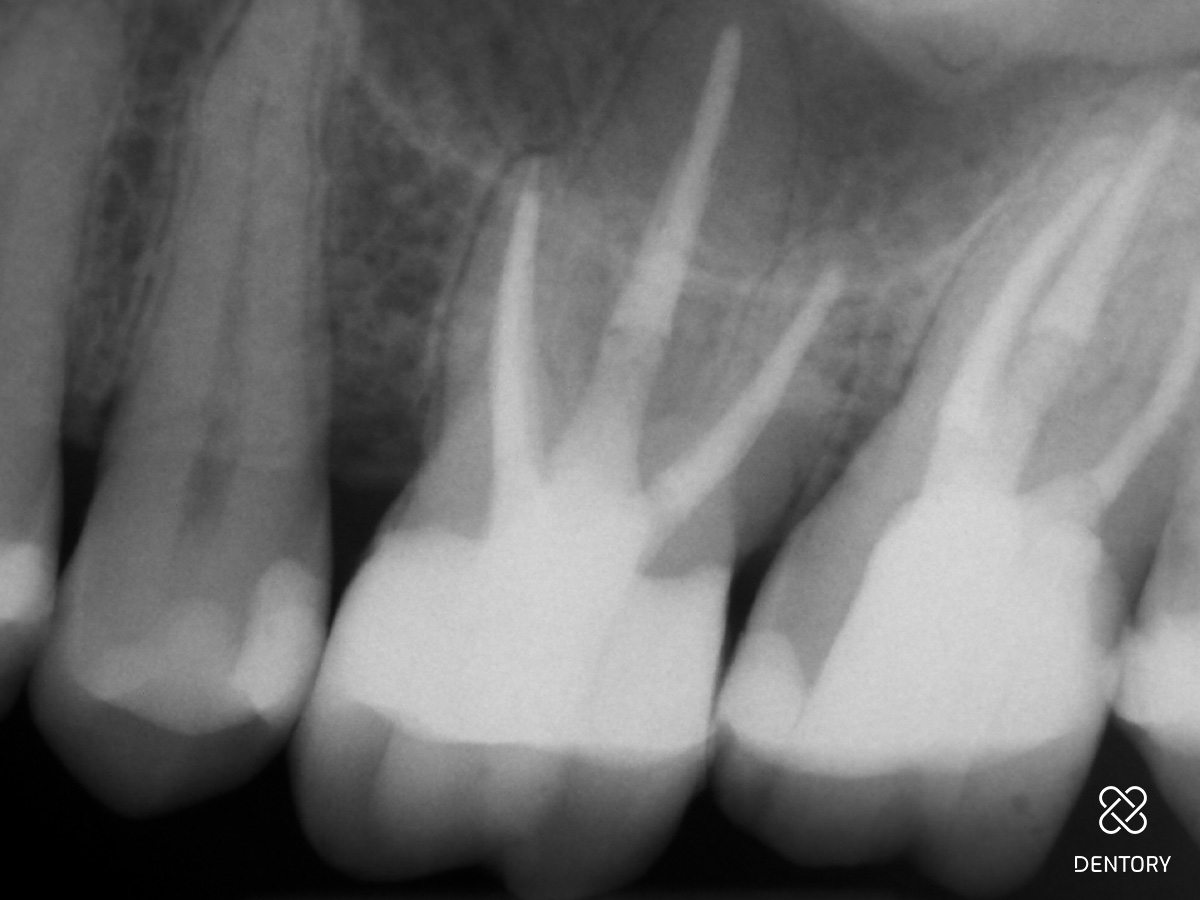

Abbildung 22

Post-OP.